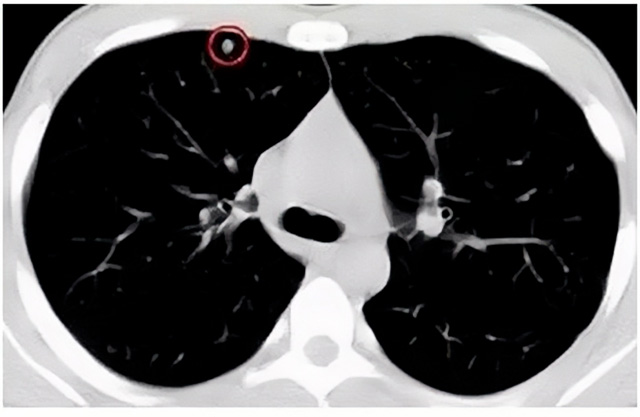

移動(dòng)CT體檢車可以做肺部檢查。隨著多層螺旋CT肺部低劑量掃描的臨床應(yīng)用,目前很多人選擇肺部CT作為常規(guī)檢查項(xiàng)目,較大地提高了肺結(jié)節(jié)的檢出率。如果檢查發(fā)現(xiàn)肺部有肺結(jié)節(jié)是磨玻璃型的,小于5mm的微小結(jié)節(jié),大部分都是良性的。如果達(dá)到1CM以上的,很有可能有肺癌的機(jī)率。根據(jù)其內(nèi)密度不同可分為磨玻璃結(jié)節(jié)、實(shí)性結(jié)節(jié)、部分實(shí)性結(jié)節(jié)。根據(jù)其大小可分為肺大結(jié)節(jié)、小結(jié)節(jié)和微小結(jié)節(jié)。如果是炎癥性肺結(jié)節(jié),幾個(gè)月后復(fù)查有變化變小就不用做手術(shù)。如果CT再次復(fù)查結(jié)節(jié)沒有變化,沒有縮小就需要升級做病例檢查。病理檢查的確診性是最高的。是有沒患癌的標(biāo)準(zhǔn)。檢查發(fā)現(xiàn)早的話,規(guī)范手術(shù)治療,手術(shù)后5年的存活率很高的。肺癌這個(gè)要早發(fā)現(xiàn)早治療。

現(xiàn)在的移動(dòng)CT體檢車的分辨率比X光高,CT掃描的圖像越來越薄顯像更清晰,檢查更準(zhǔn)確。得到了普及,肺結(jié)節(jié)的測出率很高的。但是顯浩告訴大家,肺結(jié)節(jié)不等于肺癌。雖然很多是良性,但是很多肺癌都是肺結(jié)節(jié)發(fā)展來的。 必須定期檢查復(fù)查。磨玻璃結(jié)節(jié),肺癌的機(jī)率較高。肺癌是惡性腫瘤病死率最高的。除了環(huán)境,遺傳,等因素。吸煙,從事煙霧工作行業(yè)的人員比較危險(xiǎn)。發(fā)病比例高。肺部疾病早發(fā)現(xiàn)早治療,依舊是肺部疾病的治療標(biāo)準(zhǔn)。

一旦CT檢查發(fā)現(xiàn)肺結(jié)節(jié),若不規(guī)律復(fù)查,檢查等同于白檢。所以在復(fù)查中,如果結(jié)節(jié)中發(fā)現(xiàn)有增大的趨勢,或大小發(fā)生了變化,我們必須提請注意及時(shí)治療,不要掉以輕心。移動(dòng)CT體檢車的普及化,讓肺部檢查更準(zhǔn)確更高效。發(fā)現(xiàn)肺結(jié)節(jié)時(shí),及時(shí)就醫(yī)并進(jìn)行專業(yè)評估是確保準(zhǔn)確分類和采取適當(dāng)措施的關(guān)鍵。